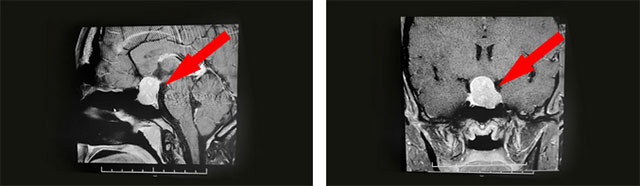

經(jīng)過(guò)醫(yī)院仔細(xì)檢查發(fā)現(xiàn):鞍區(qū)MRI平掃+增強(qiáng)顯示:蝶鞍擴(kuò)大,鞍底骨質(zhì)下陷;鞍內(nèi)垂體可見(jiàn)類(lèi)橢圓形異常信號(hào),大小約2.5*1.6cm,垂體柄未見(jiàn)明顯顯示;鞍上結(jié)構(gòu)尚清,視交叉上抬;病灶與雙側(cè)海綿竇分界清晰;所示蝶竇局部黏膜增厚。

▲ 影像檢查顯示:垂體大腺瘤,超蝶鞍生長(zhǎng)